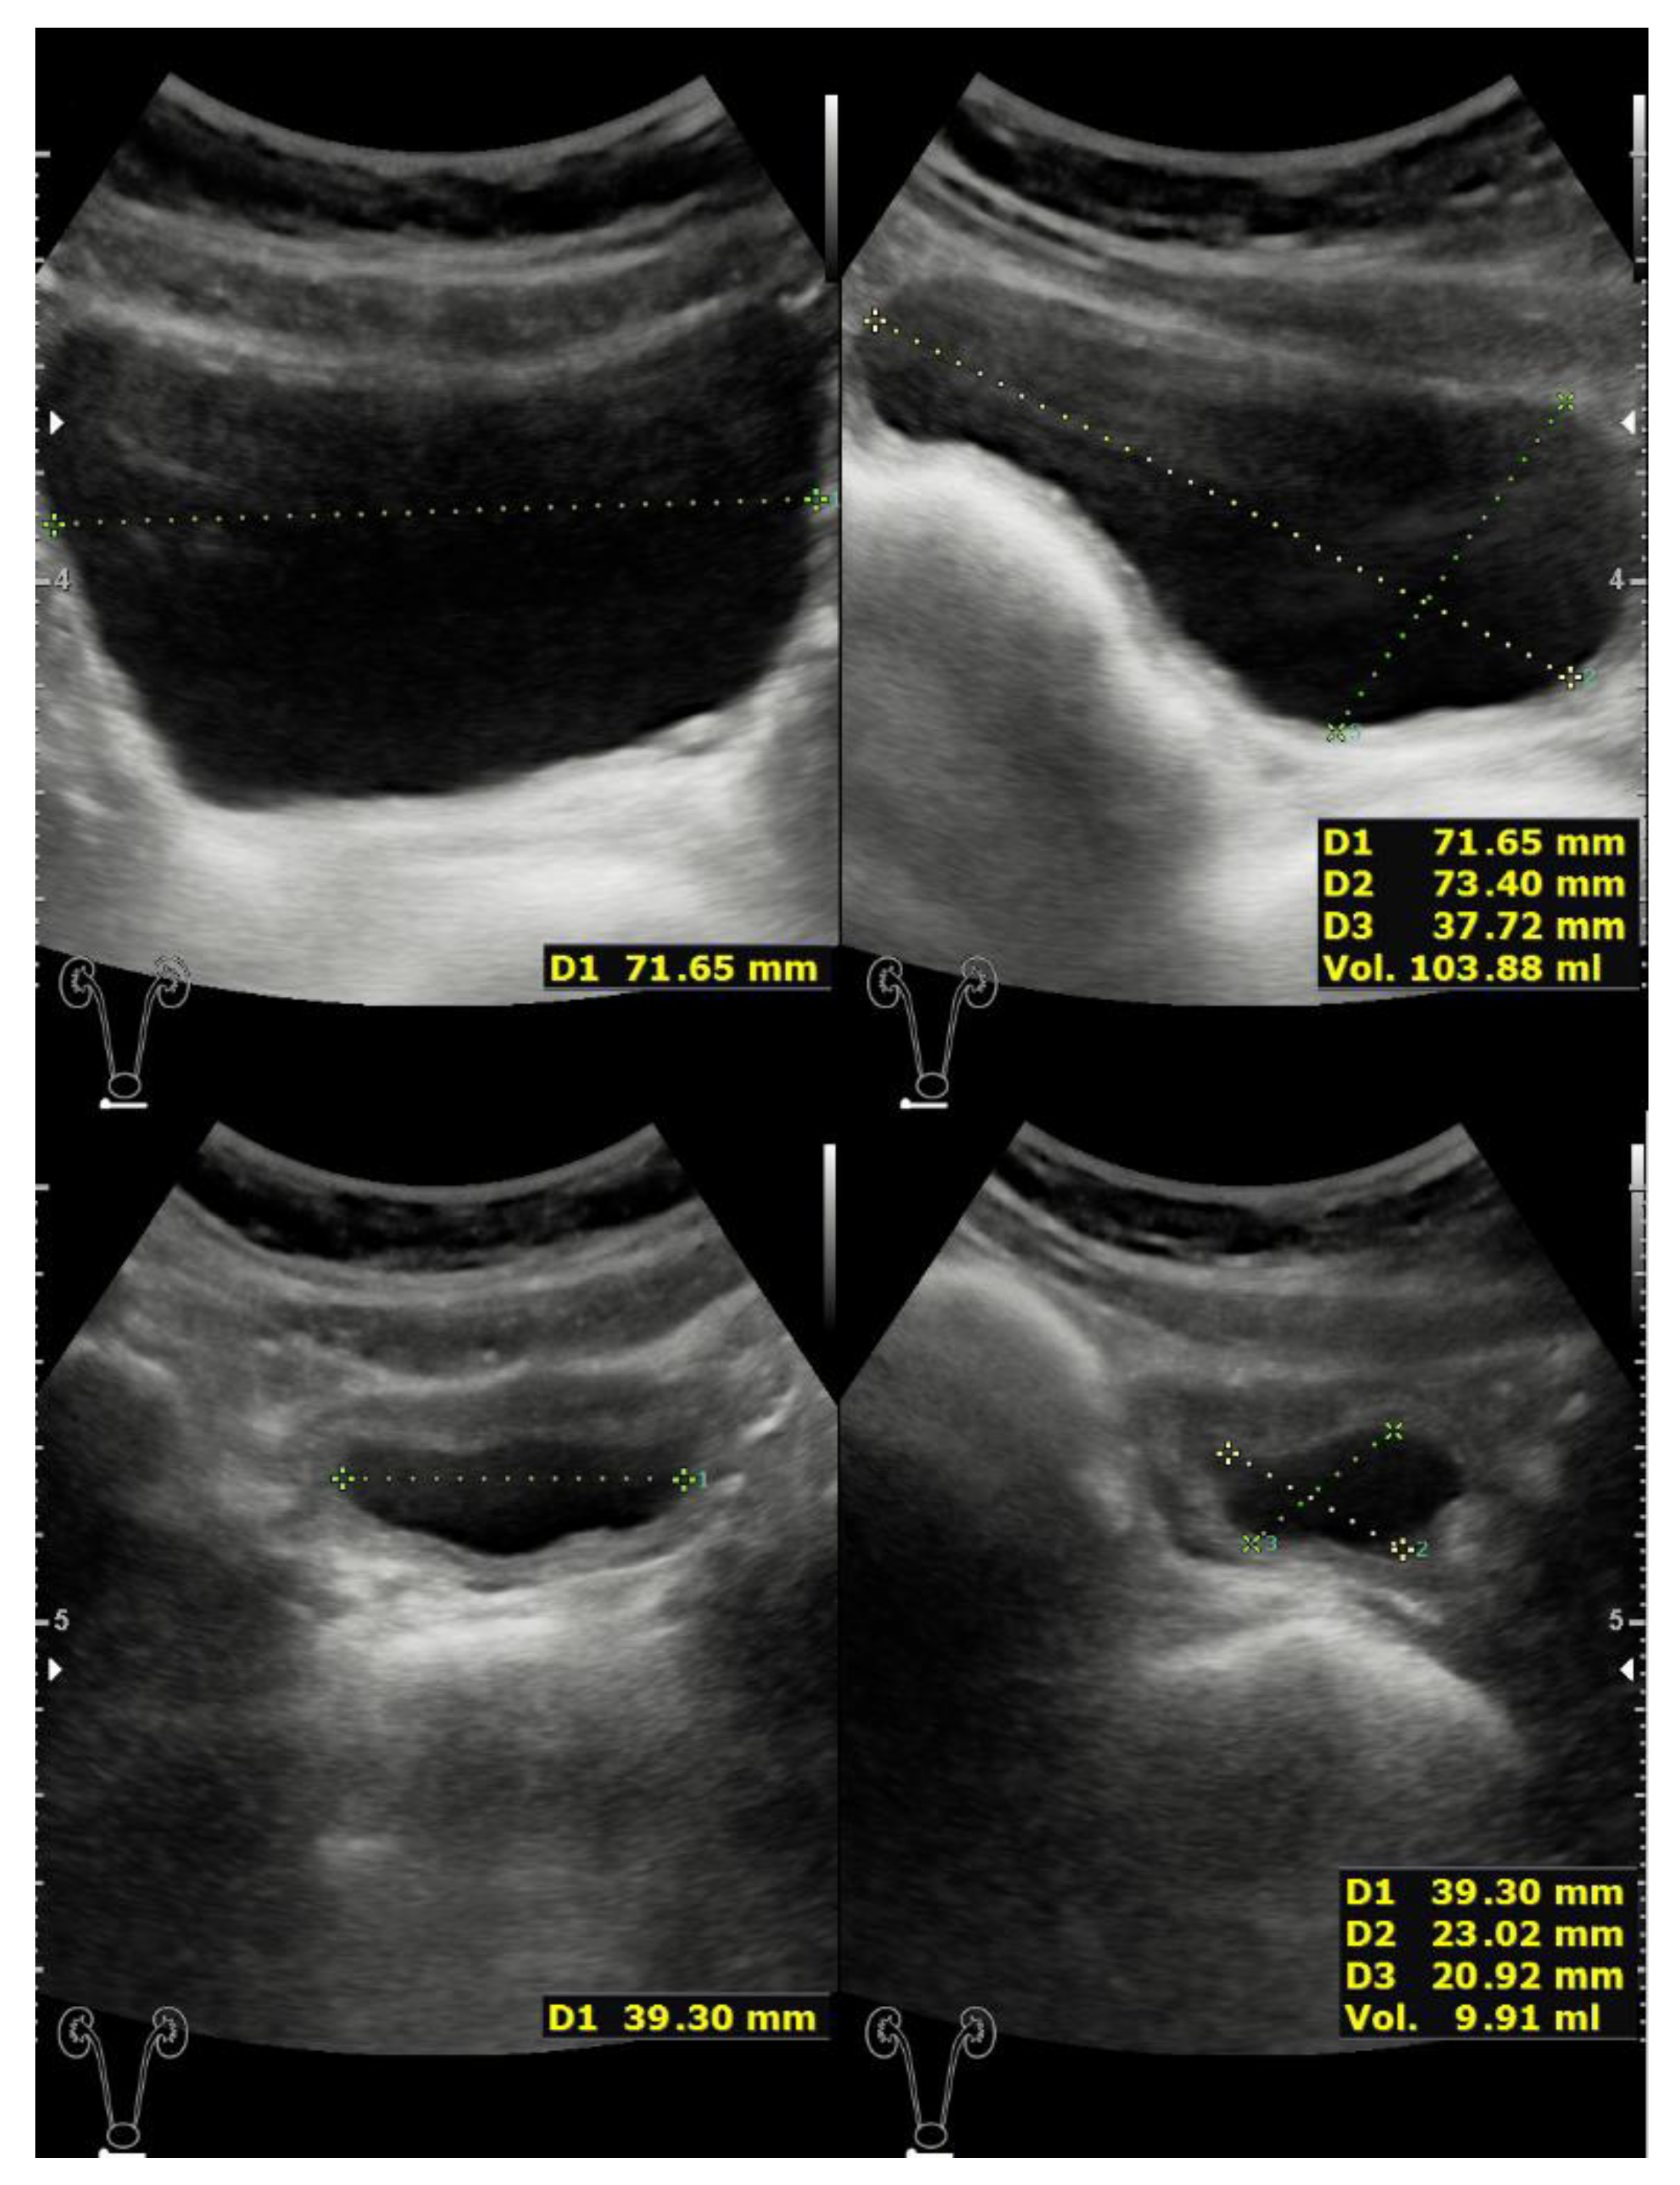

2.1. Case 1